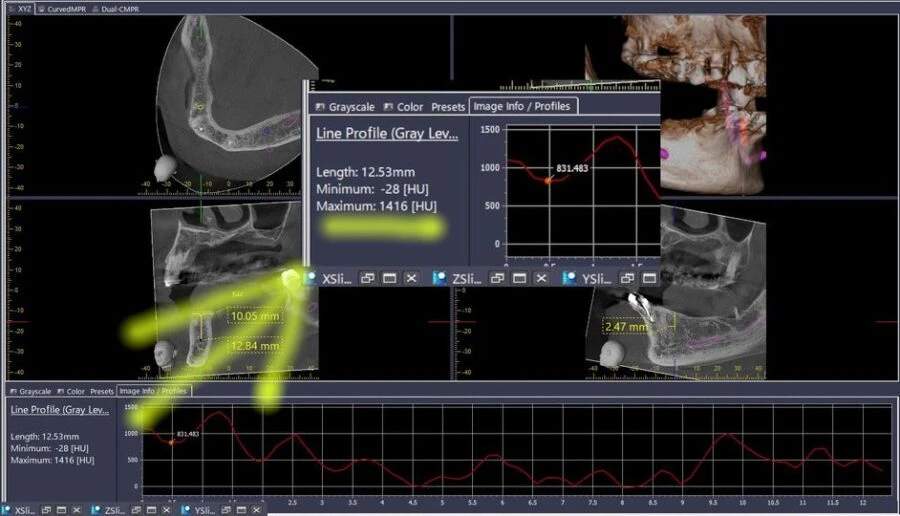

Điều đặc biệt của HU đối với thiết bị CBCT

Ứng dụng của HU trong CBCT rất quan trọng, chẳng hạn, khi khảo sát phim của một Implant mới cấy, đường đồ thị thể hiện chất lượng xương (HU) từ lớp xương vỏ, cắt ngang qua thân Implant có thể dễ dàng cho thấy sự tích hợp của xương quanh thân Implant đó như thế nào.

Bạn có thể tự mình kiểm chứng điều này khi sử dụng thang đo Profile trên các phần mềm CBCT (hay thang HU trên phần mềm i-Dixel Morita).